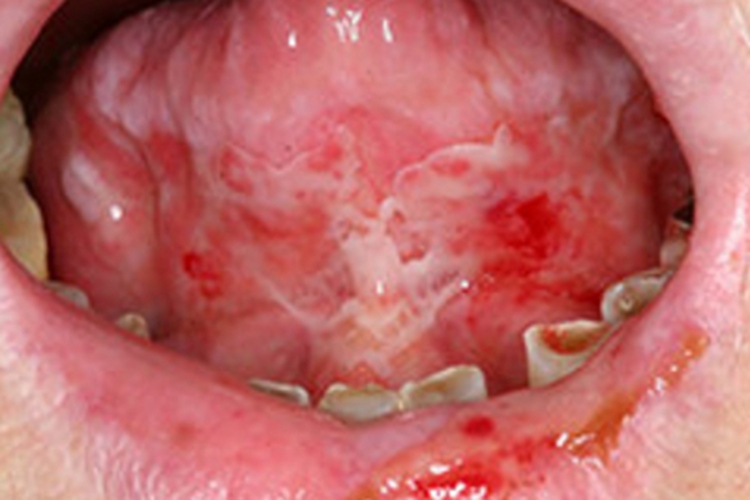

副肿瘤性天疱疮可出现不规则的溃疡,呈白色,周围充血、肿胀,伴渗血,常自觉疼痛,可遵医嘱进行手术或药物治疗。

副肿瘤性天疱疮可见不规则的白色溃疡面,周围充血、肿胀,伴渗血,绕以红晕,口内分泌物增加,患者有剧烈疼痛,分布较光焰,严重时可累及多处黏膜。